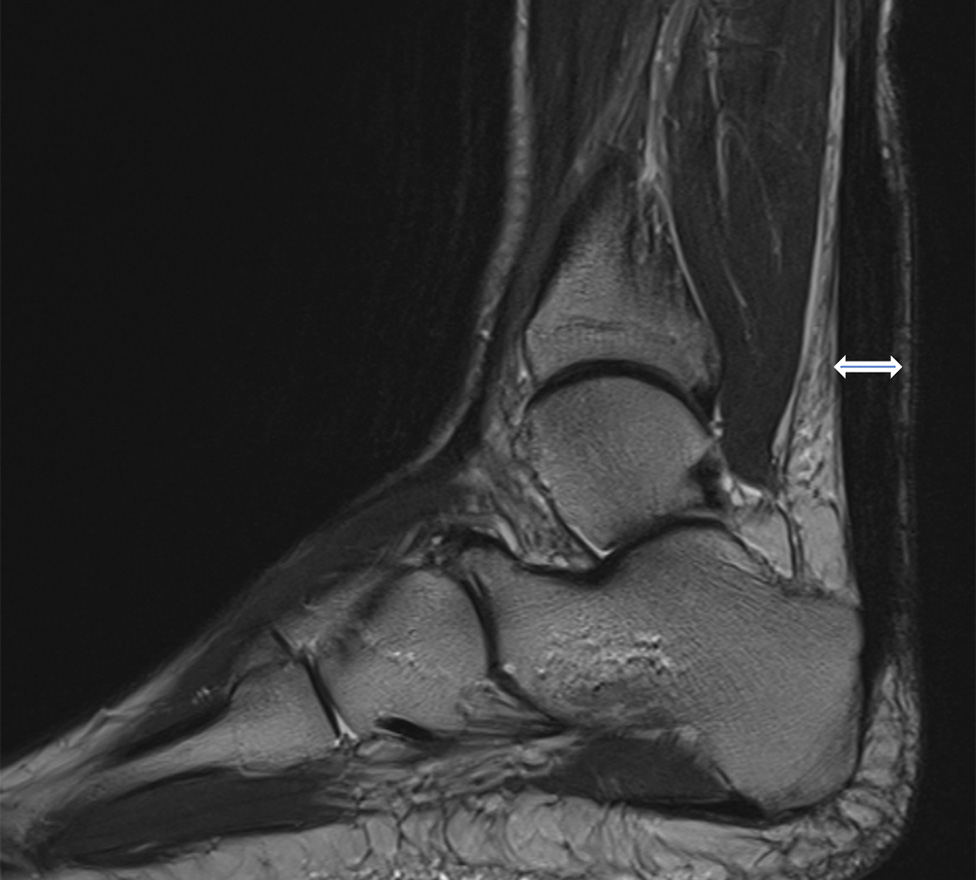

Die Diagnose einer Peronealsehnenverletzung lässt sich in der klinischen Untersuchung bereits erahnen. Beweisend ist jedoch die sichtbare Verletzung durch eine Magnetresonanztomographie (MRT bzw. engl. MRI für magnetic resonance imaging) *.

Bild: Universitätsklinik Balgrist